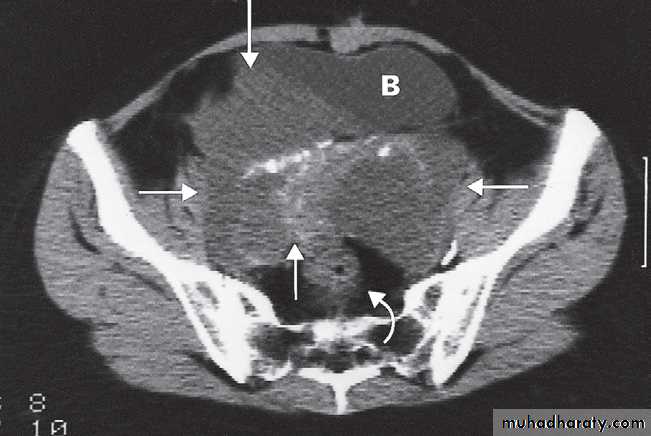

Malignant ovarian masses

• Mixed solid and cystic mass.

• Vascularity within solid components on Doppler.

• Thickened septations, >3 mm.

• Large size.

• Bilateral masses.

• Associated ascites or peritoneal deposits.

MRI may be used to further characterize indeterminate masses as benign or malignant prior to deciding on patient management. With disseminated malignancy, deposits within the omentum and ascites may be visible .

Ultrasound, CT and MRI may show hydronephrosis from ureteric obstruction by the tumour and may also demonstrate enlarged lymph nodes, liver metastases or pleural effusions.